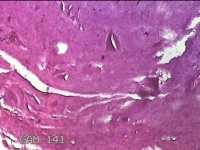

右侧中指指间关节背侧包块

性别

男

年龄

46岁

临床诊断

皮下结节

一般病史

发现右侧中指指间关节背侧一包块,伴间断性疼痛不适,考虑痛风结节。

标本名称

大体所见

灰白粉红色包块0.8x0.7x0.3cm一堆。

图3